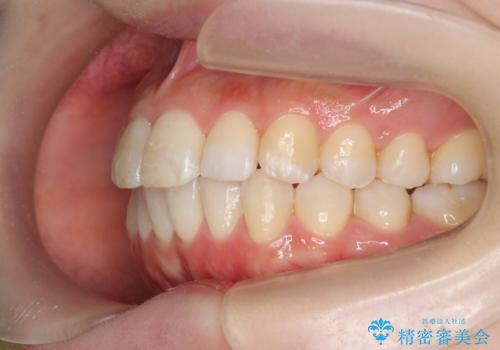

インビザラインで出っ歯の治療

- 「目立つ前歯の出っ歯をなんとかしてほしい。」と矯正治療を希望され来院されました。

突出した上顎の前歯に加え、ガタつきの目立つ下顎の歯列も同時にマウスピース矯正インビザラインで整えていきます。

突出間(所謂 出っ歯)のある前歯の位置は大幅に改善され、審美性が大きく向上しました。

加えて奥歯も噛み合わせも良くなったことで、咬合状態が安定しより安定した歯列を獲得することができました。